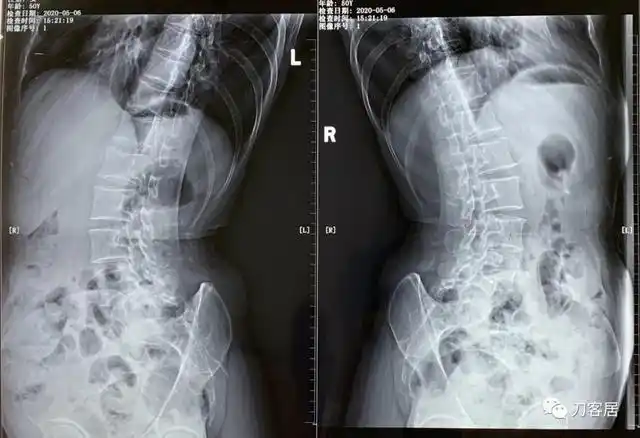

51岁,女,腰痛并左下肢痛麻,半年后右下肢麻痛,诊断腰椎滑脱